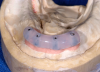

To adequately relieve the denture in the area of the implants, an impression and bite registration material was placed on the intaglio surface of the prosthesis, and then the prosthesis was placed over the overdenture abutments.41 The prosthesis was removed from the mouth after the polymerization of the impression material. The indentations of the denture caps were registered in the impression material (Figure 13). A vent hole bur was used to drill straight through the center of the indentations (Figure 14, top).41 A recess bur that fitted right in the hole was used to open the spaces (Figure 14, bottom). Next, retention was created by using an inverted cone retention bur.41 Then a round bur, football-shaped bur, and polisher were used to finish and polish the recesses.41

Fig 13. Indentations of abutments registered in the impression material.